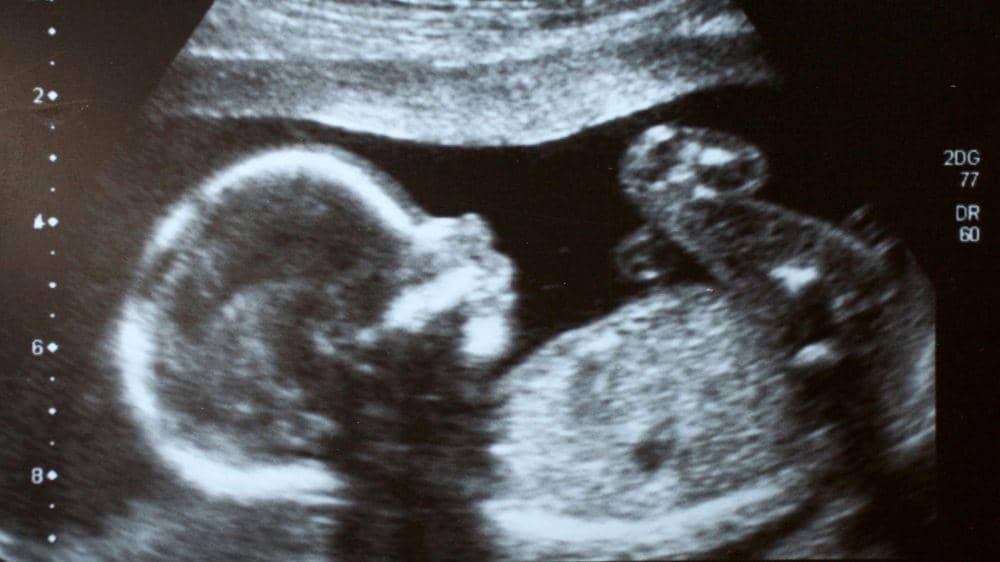

3. Mereka mulai berlatih gerakan bayi

Sebelum keluar dari rahim, bayi sudah melatih kemampuan motoriknya. Misalnya memasukkan jari ke mulut, belajar menggenggam, bahkan tersenyum.

7. Bayi bisa berguling di dalam rahim

Bayi tidak selalu bisa mengontrol gerakannya di dalam rahim. Selain itu mereka juga banyak terpengaruh oleh aktivitas ibunya. Misalnya, saat ibu tertawa bayi akan memantul ke atas dan ke bawah. Ketika sang ibu berlari, bayi akan berguling mengikuti gerakan tersebut.